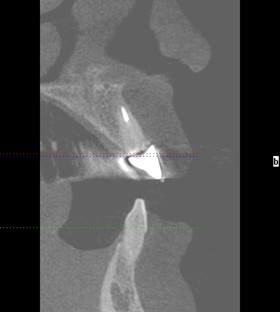

The increasing demand for efficient and minimally invasive tooth replacement options has driven the adoption of immediate implant placement. Within the framework of a patient-centered and comprehensive treatment plan, selecting the appropriate timing for implant placement is a crucial determinant of overall treatment success. Unlike delayed implant placement, which requires several months of healing after extraction, IIP involves placing the implant directly into the fresh extraction socket (Figures 1 and 2). This technique not only reduces the number of surgical interventions and associated patient morbidity but also allows for immediate implant-supported fixed restorations if conditions permit. It significantly reduces both chair time and overall treatment duration compared to other protocols (Puisys et al., 2022). Advances in surgical protocols, digital diagnostics, and implant design have made IIP increasingly predictable, particularly when combined with immediate temporization. However, the clinician must weigh these benefits against the increased technical demands and biological complexities inherent in the procedure. The ITI SAC Classification Tool (Straightforward, Advanced, Complex) helps stratify cases by risk and complexity, thereby guiding appropriate case selection and operator readiness (Morton et al., 2023).

Fig. 1a: CBCT of initial situation with non-restorable tooth 21